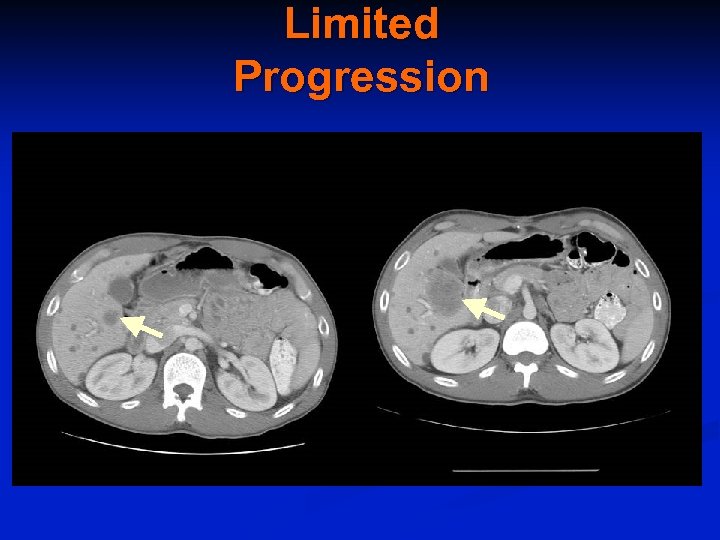

Type of Progression Limited progression Nodular progression Stable disease Stable lesion Progressing lesion Widespread progression

Limited Progression

Therapy by Type of Progression n Limited or Nodular Progression Hepatic Artery Embolization n Hepatic Radio-frequency Catheter Ablation n Surgical Resection n n Widespread progression Increase Imatinib to 800 mg daily n Sunitinib n Clinical Trial n